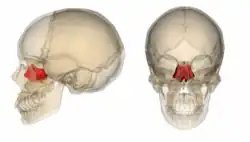

A caixa craniana é formada pelos seguintes ossos:

Osso temporal (par)

Osso temporal (par) -